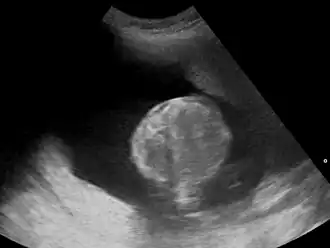

Многоводие (синоним греч. полигидрамнион) — патологическое состояние, при котором наблюдается избыток околоплодных вод в амниотической полости. По статистике, наблюдается у 1 % беременных женщин[3][4][5]. Существует два типа многоводия:

Симптомами многоводия являются увеличение размеров матки, увеличение высоты стояния дна матки над лоном в сравнении с нормативными показателями, увеличение длины окружности живота в сравнении с нормативными показателями, напряжение матки, тугоэластическая консистенция матки, флюктуация, повышенная подвижность плода.